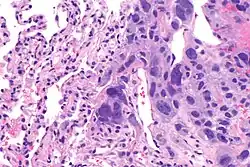

Yolk sac tumor

The ovarian yolk sac tumors, also known as endodermal sinus tumors, are accountable for approximately 15.5% of all OGCTs.[8] They have been observed in women particularly in their early ages, and rarely after 40 years of age.[9] The critical pathologic features are a smooth external surface and capsular tears due to their rapid rate of growth. A study consisting of 71 individual cases of ovarian yolk sac tumor provides evidence to the proliferation of the tumor. In one of the cases, the pelvic examination revealed normal activity until a 9 cm and 12 cm sized tumor was discovered 4 weeks later.[9] In another case, a 23 cm tumor was discovered in a pregnant woman who was monitored regularly and had normal findings until oophorectomy became essential.[9] Histologically, these tumors are characterized by mixed solid and cystic components.[1] The mixed solid components are characterized by a soft gray to yellow solid components accompanied with significant hemorrhage and necrosis. The cysts are approximately 2 cm in diameter and populated throughout the tissue which results in giving the neoplasm a ‘honeycombed appearance’.[1]